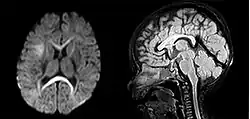

In research, cranial height or brain imaging may be used to determine intracranial volume more accurately.[2]